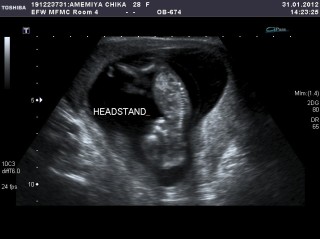

まさかの逆立ちベイベー!

看護婦さんが”Headstand”とコメント入れてくれましたw

その後は普通の体勢に戻って、手を握ったり開いたり!